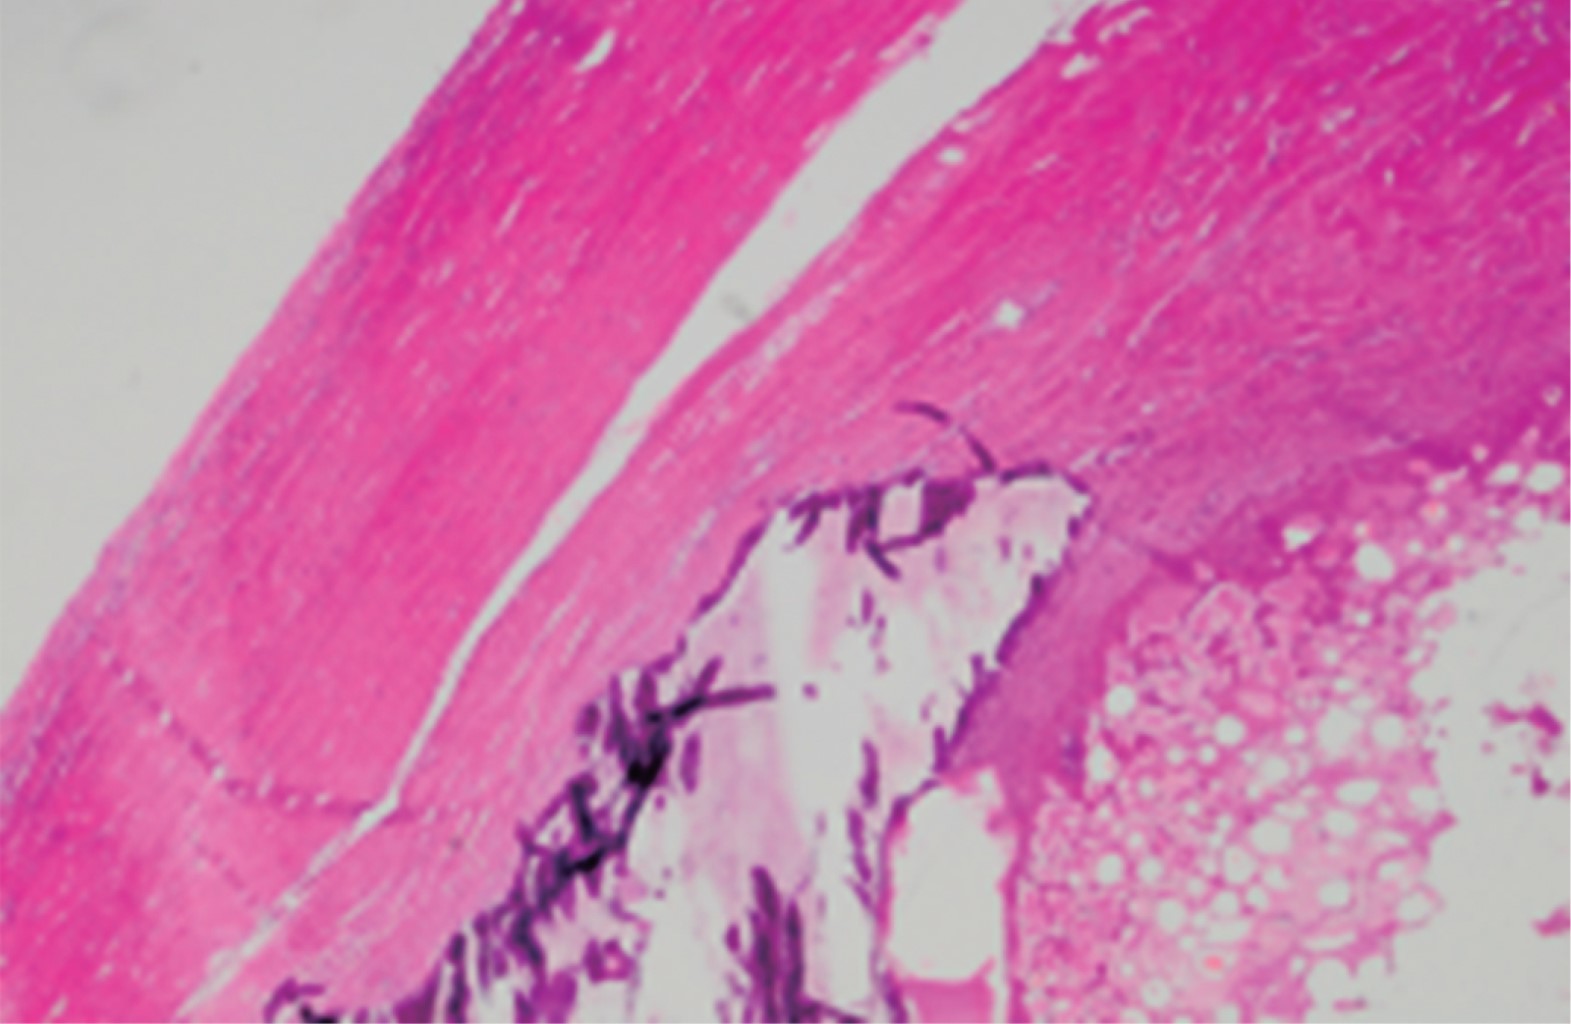

El análisis patológico macroscópico reportó tres neoformaciones ovoides de 17 × 15 × 10 mm, 16 × 10 × 10 mm y 14 × 10 × 10 mm cada uno, de superficie lisa, amarilla y firme (Figura 3); al corte son sólidos, con una zona periférica gris blanquecina de 4 mm de espesor y una zona central amarillenta de consistencia firme (Figura 4).

La descripción microscópica consiste en apéndices epiplóicos con tejido conectivo denso en la periferia, con calcificación distrófica y zonas de necrosis grasa, sin otro tipo de alteraciones ni cambios histológicos de tipo neoplásico maligno. Apendicitis aguda fibrinopurulenta (Figura 5).